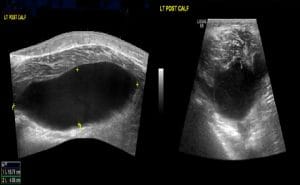

POCUS of the lateral aspect of the patient’s left leg demonstrated a 1.6×1.1cm non-compressible, non-pulsatile hypoechoic area with irregular borders likely represents a collection using bedside ultrasound (Figure 2). After that, intravenous flucloxacillin, Benzylpenicillin and Clindamycin were started to treat the collection (abscess) within the muscle as per local guidelines.

Figure 2. 1.6×1.1cm non-compressible, non-pulsatile hypoechoic area with irregular borders within left lateral gastrocnemius muscle confirming presence of fluid.